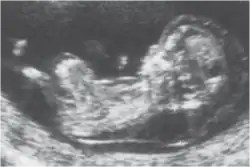

Clarté nucale

La clarté nucale, petite zone anéchogène (ne renvoyant pas d'écho en échographie) située sur le crâne d'un fœtus humain pendant le premier trimestre de grossesse, permet de dépister certaines anomalies congénitales, en particulier la trisomie 21.

La clarté nucale, comme son nom l’indique, se situe au niveau de la nuque du fœtus. Elle est due à un petit décollement entre la peau et le rachis et correspond à une zone dite anéchogène (c’est-à-dire qui ne renvoie pas d’écho lors de l’examen). Tous les fœtus présentent une clarté nucale au cours du premier trimestre, mais cette clarté disparaît ensuite.

La mesure de la clarté nucale[6] doit avoir lieu au cours de la première échographie de la grossesse, c’est-à-dire entre la 11e semaine et 13 semaine + 6 jours d’aménorrhée. Il est impératif que l’examen soit fait à cette période, car passé trois mois, la clarté nucale disparaît.